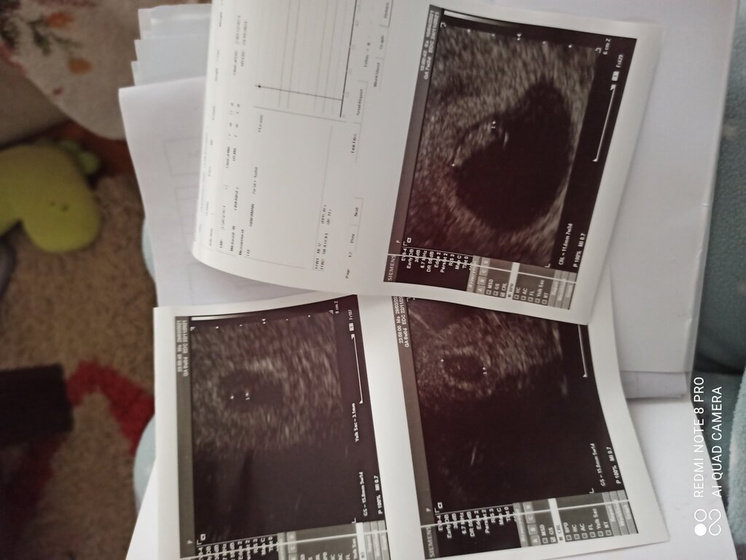

И вот подошла к концу наша 9я неделька ????